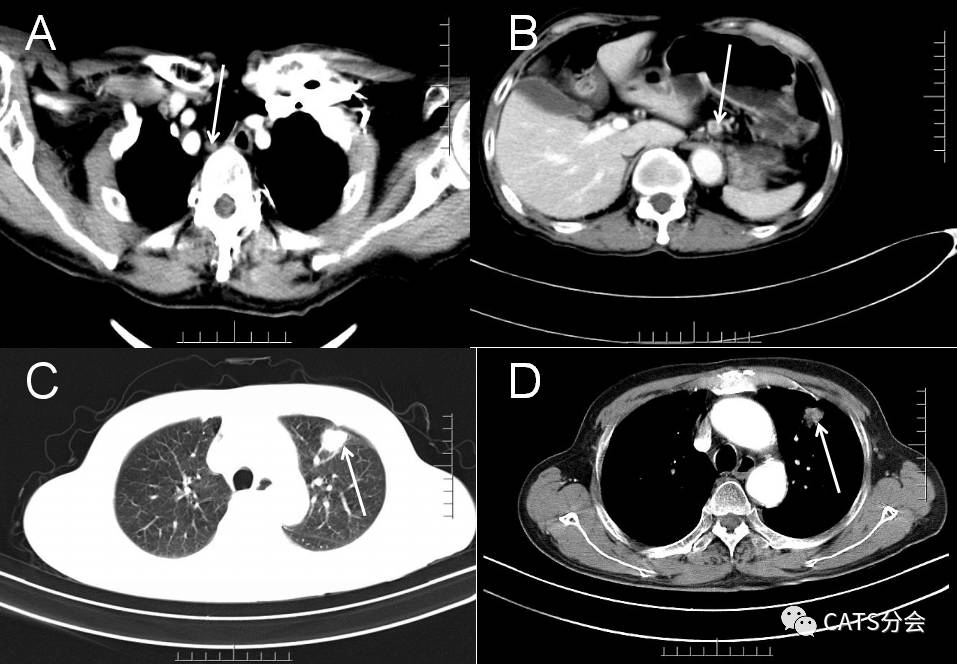

患者男,71岁,因进行性吞咽困难5月,发现左肺上叶结节增大2月入院。患者2月前就发现食管胸下段及左肺上叶病变,一直选择观察,未做特殊治疗。现复查CT发现病变较前增大,要求行手术切除,拒绝放化疗。查超声胃镜:食道距门齿35--40cm见一环周低回声肿物,浸润食道固有肌层及部分外膜,最厚约10.6mm。胸腹部CT提示(图1):胸下段食管壁较前增厚,较厚处约为1.2cm,右喉返神经旁、胃底周围淋巴结肿大;左上肺结节较前稍增大,大小约2.3*1.9cm,边缘分叶毛刺,考虑原发肺癌可能性大。全身检查未发现转移及其他手术禁忌症。

图1. A. 右侧喉返神经旁见淋巴结显示,直径5mm;B. 胃左淋巴结肿大,直径10mm;C,D. 左肺上叶肿物,根据影像学特征考虑原发肺癌可能性大。